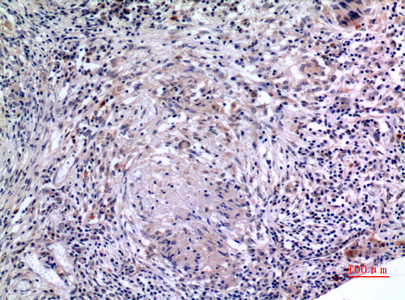

产品名称IL-6 Rabbit Polyclonal Antibody

推荐应用WB,IHC-P,IF-P,IF-F,IF-ICC,ELISA

稀释度WB 1:500-1:2000, IHC-P 1:100-300, ELISA 1:20000, IF-P/IF-F/IF-ICC 1:100-300, Not yet tested in other applications.